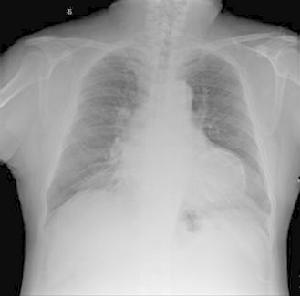

(1)除描記12導聯心電圖外:應加描記V7~V9,V3R~V5R等導聯,必要時高一肋間或降低一肋間描記,或進行胸前標記。

(2)在特徵性病理性Q波等心電圖變化之前:應注意對應導聯的ST-T改變及急性損傷區傳導阻滯等改變。

1.在相應的心肌梗死的部位,可出現典型的病理性Q波、ST-T改變等,可進行定性、定位診斷。